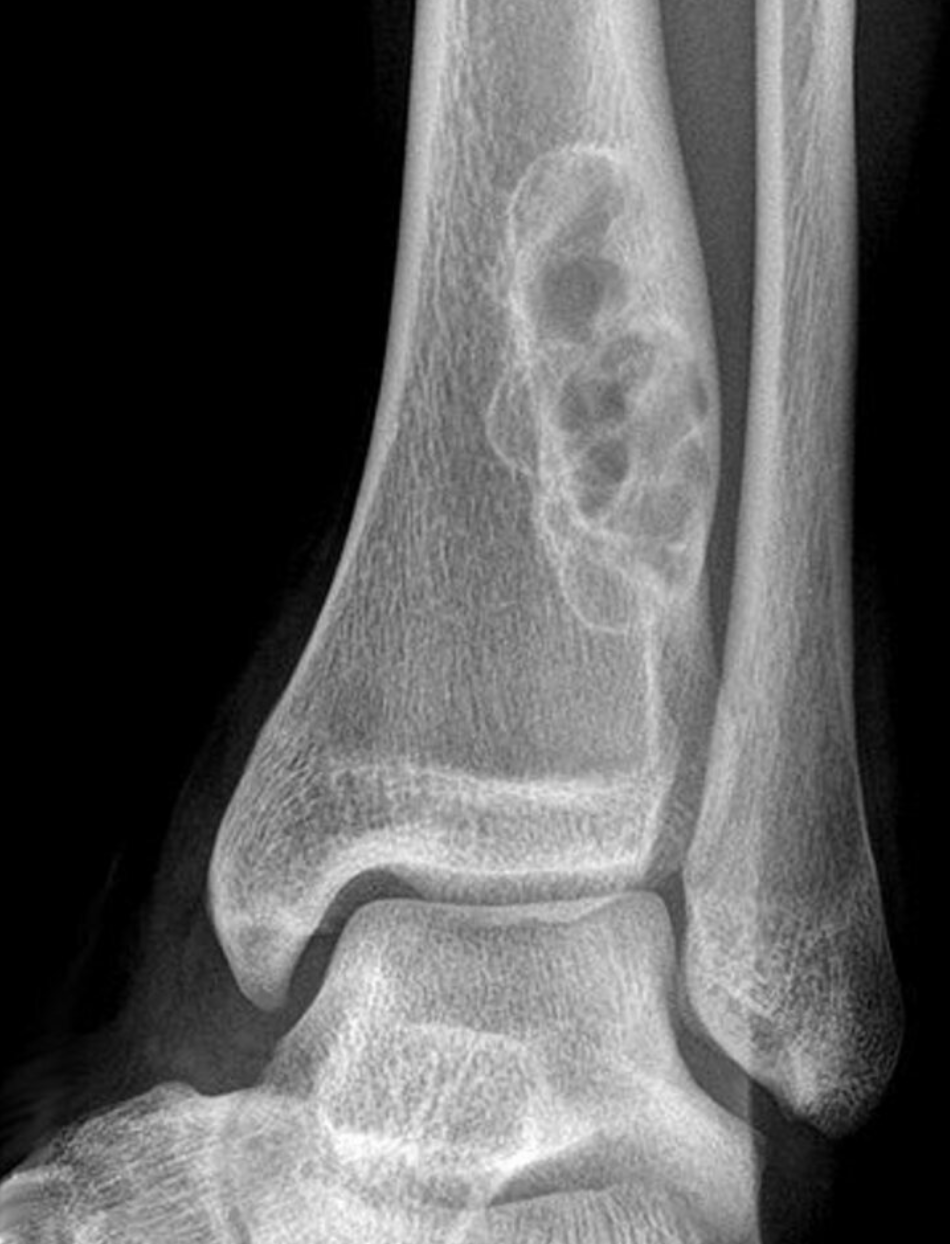

_____ shows eccentric well-lobulated lesions and sclerotic scalloped borders.

Hint: Bone tumor